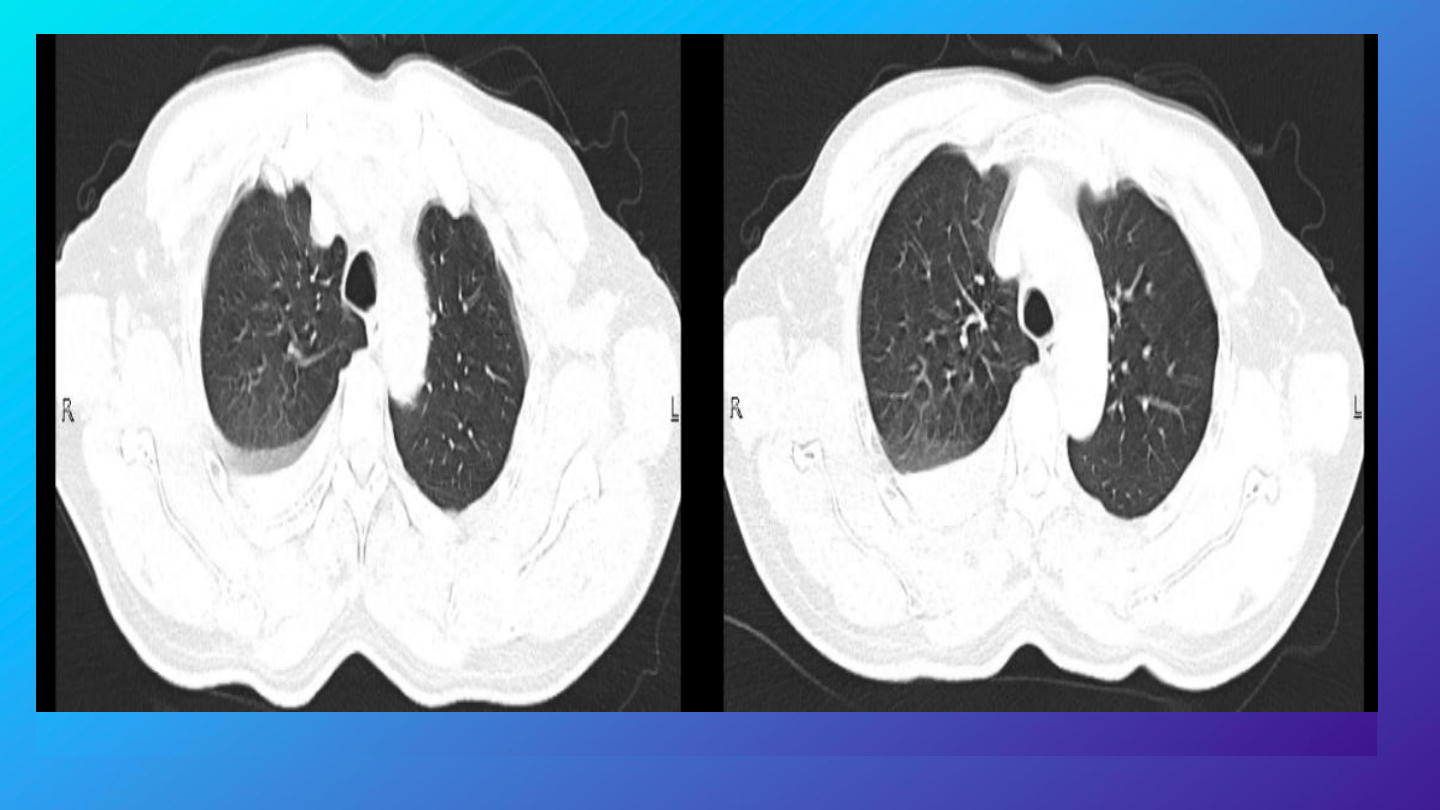

完善胸部增强

右侧胸腔积液、积血,较前片

2024-10-22 10:20

)积液、积血

增多,请结合临床;

右肺下叶肺不张,右肺各叶及左

肺下叶炎性渗出改变。

右侧第

5

6

前肋骨皮质略褶皱。